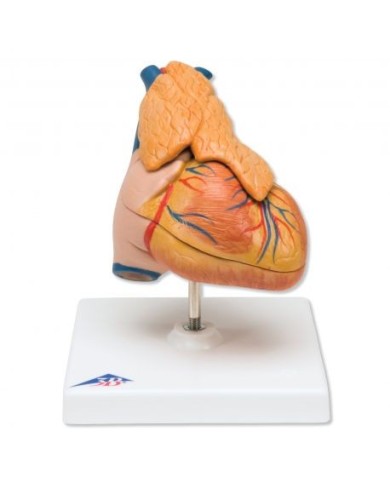

Modello anatomico di cuore, ingrandito 2 volte, su cavalletto

Questo modello dettagliato mostra, oltre alle strutture anatomiche del cuore, anche una parte del diaframma (base)